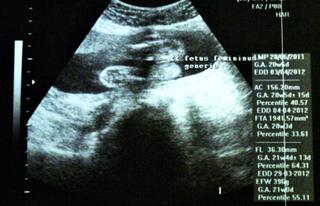

No ale toto som chcela: včera sme mali morfo sono...všetko super ako má byť...dokonca sa nám to naše malé drobča ukázalo a pán doktor povedal že vidí kávové zrnko🙂 s manželom sme sa usmiali a potom to ešte potrvdil, rýchlim 3D-čkom takže MÁME MALÚ PRINCEZNÚ V BRUŠKU !!! tešime sa moc...a dokonca vraj bude mať dlhé nohy, čo som ja vždy chcela, preto sa tešim eśte viac 🙂 Má takmer 400 g podľa počitača 🙂

Inak ak aj vy máte takéto snímky a neviete si rady so skratkami tak toto znamenajú :

BPD (priemer hlavy),

HC (obvod hlavy),

AD (priemer brucha),

AC (obvod brucha),

FL (dĺžka stehennej kosti).

G.A. (vek plodu podla meranej časti tela)

EDD (predpokladaný termín pôrodu)

len neviem co je ten percentil 🙂 vy viete?

Tu pridávam fotky našej krásavice a jej kávového zrnka 🙂